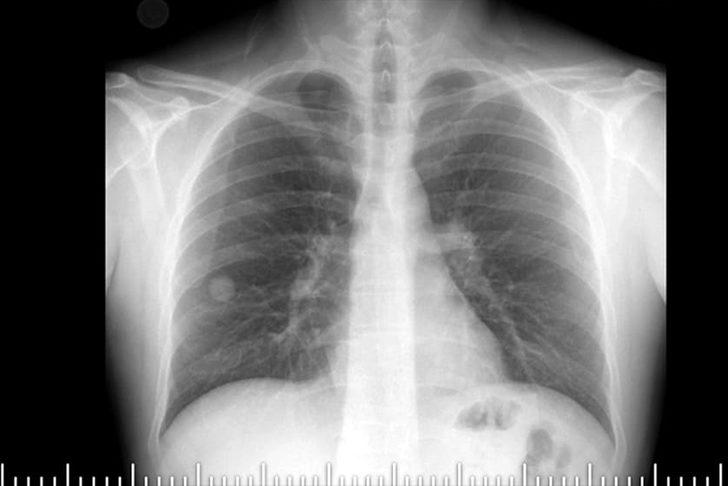

Elazığ Fethi Sekin Şehir Hastanesi Göğüs Cerrahisi Polikliniğine göğüs ağrısı ve öksürük şikayetiyle başvuran Topuz'un çekilen tomografisinde, sağ akciğer orta lobunda 2 santimetre büyüklüğünde tümör olduğu tespit edildi.

Hastanede görevli Dr. Murat Kılıç da Topuz'un şikayetleri üzerine sağ akciğerinde 2 santimetre büyüklüğünde tümör tespit ettiklerini dile getirerek, "Kitlenin boyutunda büyüme tespit edilmesi üzerine hastaya cerrahi tedavi önerdik. Sağ akciğer orta lobunda bulunan tümöral doku çıkarıldı." dedi.